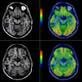

The initial analysis of RTOG 0211, a phase I/II trial of gefitinib given during and for 18 months after standard radiotherapy for glioblastoma multiforme (GBM) patients, showed that gefitinib was generally well tolerated but that survival times were not significantly improved compared to historical controls. A secondary analysis of study data is attempting to identify molecular subgroups of GBM patients that are likely to benefit from anti-EGFR therapies. Tissue microarrays generated from blocks prospectively collected on 74 of the 148 patients entered on RTOG 0211 were used to analyze the predictive values of 12 molecules integral to EGFR signaling. Using this molecular data, a multivariate risk model was developed using both clinical and molecular data that appears to identify distinct populations of GBM patients who may derive an overall survival benefit from the addition of Gefitinib to radiation in the upfront setting. This data strongly highlights activation of the phosphoinositol 3-kinase (PI3K) pathway at various junctions as a major resistance mechanism to gefitinib in GBMs. The results of this study may not only aid clinicians in selecting appropriate GBM patients for anti-EGFR therapies, but may also shed light into the basic mechanisms leading to treatment resistance in these most devastating tumors.